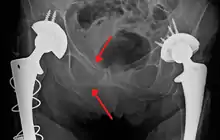

Blunt pelvic trauma

The most common causes of blunt pelvic trauma are motor vehicle crashes and multiple-story falls, and thus pelvic injuries are commonly associated with additional traumatic injuries in other locations.[28] In the pelvis specifically, the structures at risk include the pelvic bones, the proximal femur, major blood vessels such as the iliac arteries, the urinary tract, reproductive organs, and the rectum.[29][28]

.png.webp)

One of the primary concerns is the risk of pelvic fracture, which itself is associated with a myriad of complications including bleeding, damage to the urethra and bladder, and nerve damage.[30] If pelvic trauma is suspected, emergency medical services personnel may place a pelvic binder on patients to stabilize the patient's pelvis and prevent further damage to these structures while patients are transported to a hospital. During the evaluation of trauma patients in an emergency department, the stability of the pelvis is typically assessed by the healthcare provider to determine whether fracture may have occurred. Providers may then decide to order imaging such as an X-ray or CT scan to detect fractures; however, if there is concern for life-threatening bleeding, patients should receive an X-ray of the pelvis.[31] Following initial treatment of the patient, fractures may need to be treated surgically if significant, while some minor fractures may heal without requiring surgery.[28]

A life-threatening concern is hemorrhage, which may result from damage to the aorta, iliac arteries or veins in the pelvis. The majority of bleeding due to pelvic trauma is due to injury to the veins.[30] Fluid (often blood) may be detected in the pelvis via ultrasound during the FAST scan that is often performed following traumatic injuries. Should a patient appear hemodynamically unstable in the absence of obvious blood on the FAST scan, there may be concern for bleeding into the retroperitoneal space, known as retroperitoneal hematoma. Stopping the bleeding may require endovascular intervention or surgery, depending on the location and severity.[29]